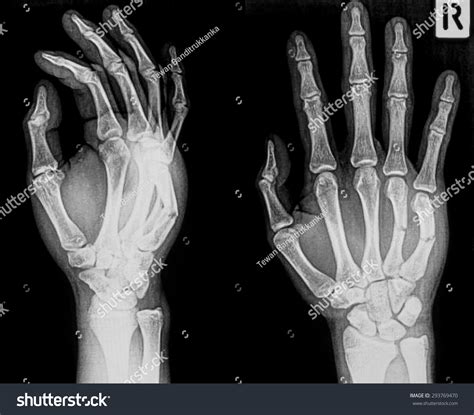

Fractured Hand Xray

Injuries to the hand are common and can range from minor cuts and bruises to more severe fractures. One of the most critical diagnostic tools for assessing hand injuries is the Fractured Hand Xray. This imaging technique provides detailed images of the bones in the hand, helping healthcare professionals to accurately diagnose and treat fractures. Understanding the process, importance, and interpretation of a Fractured Hand Xray is essential for both medical professionals and patients.

Interpreting a Fractured Hand Xray

Interpreting a Fractured Hand Xray requires specialized knowledge and training. Radiologists and orthopedic surgeons are trained to identify various types of fractures and other abnormalities in the hand. Here are some key points to consider when interpreting a Fractured Hand Xray:

• Bone Alignment: Check for any misalignment or displacement of the bones.

• Fracture Patterns: Identify the type of fracture, such as transverse, oblique, or comminuted.

• Soft Tissue Involvement: Look for any signs of soft tissue damage or swelling.

• Joint Involvement: Assess whether the fracture extends into the joints, which can affect treatment and recovery.

Radiologists use these observations to provide a detailed report that guides the treatment plan.

Common Types of Hand Fractures

Hand fractures can vary widely in terms of location, severity, and treatment requirements. Some of the most common types of hand fractures include:

• Boxer’s Fracture: A fracture of the fifth metacarpal bone, often caused by punching a hard object.

• Bennett’s Fracture: A fracture of the base of the first metacarpal bone, which can affect the thumb’s movement.

• Mallet Finger: A fracture or tendon injury that causes the tip of the finger to bend downward.

• Phalangeal Fractures: Fractures of the bones in the fingers, which can occur in any of the three phalanges.

Each type of fracture has its own set of symptoms and treatment options, making accurate diagnosis through a Fractured Hand Xray essential.